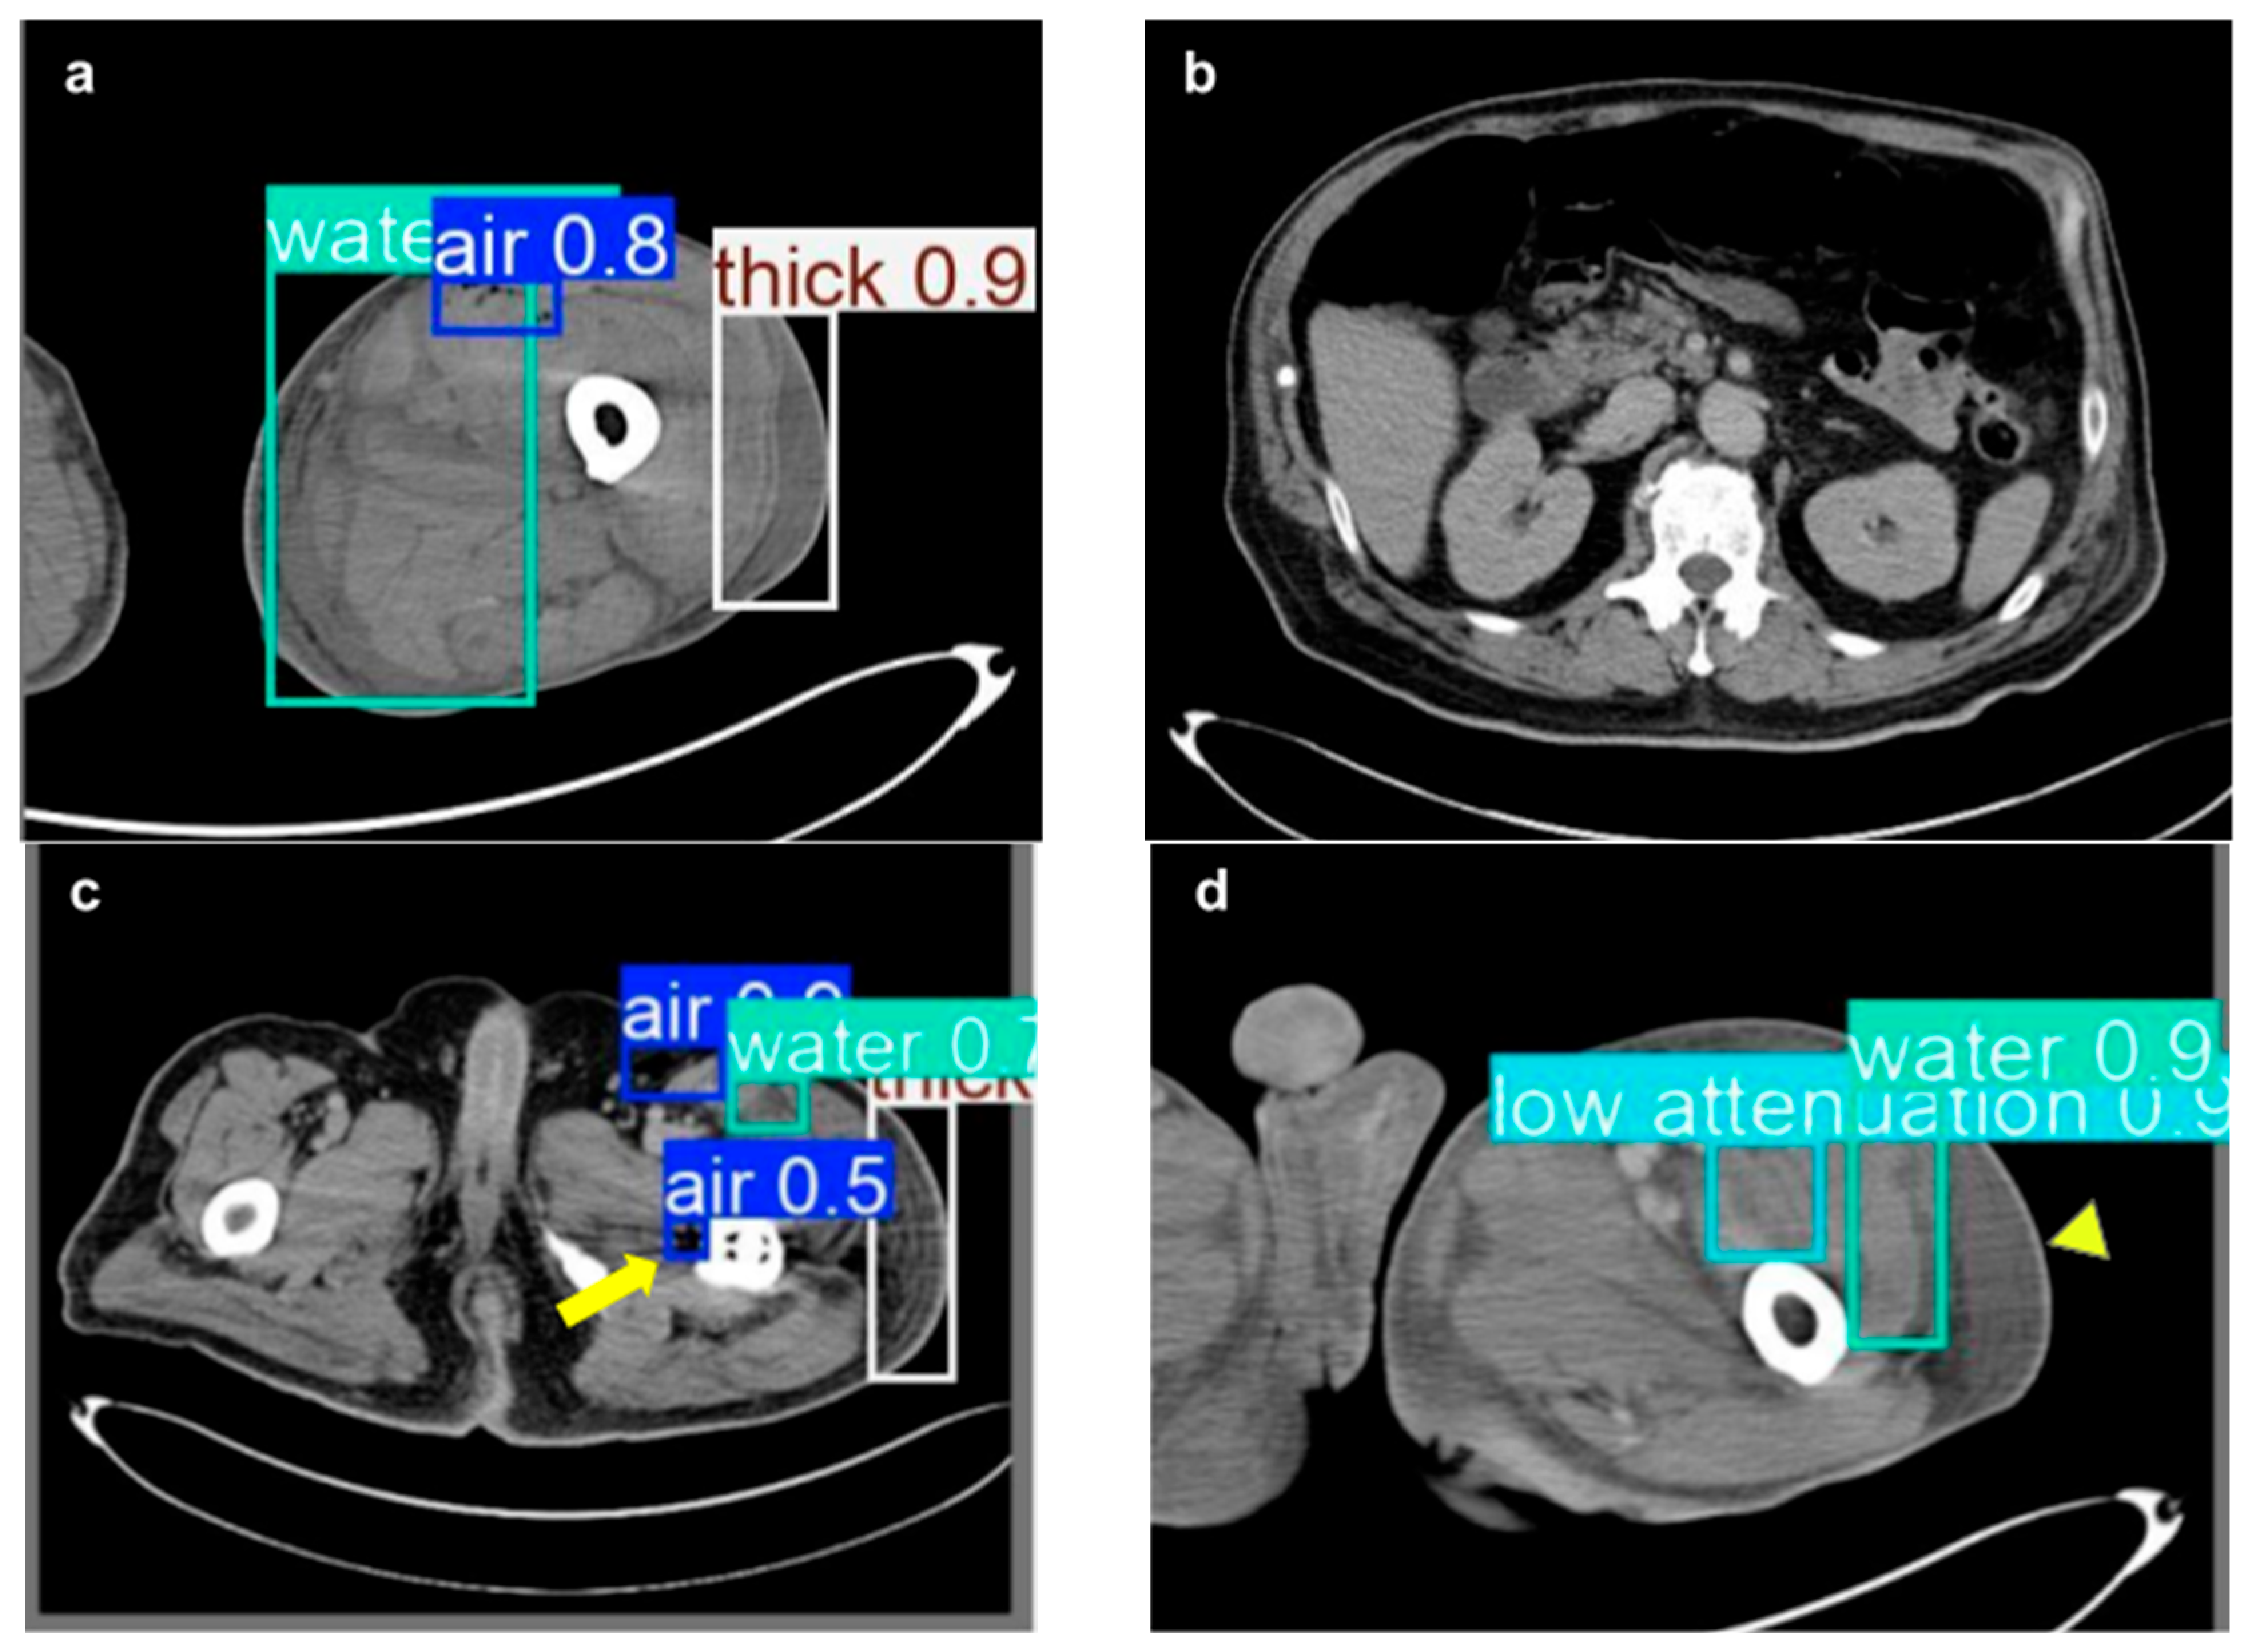

| NSTI features | ||

| Soft tissue ectopic gas | 1982 | 33.13% |

| Fluid accumulation | 1577 | 27.04% |

| Fascia edematous changes | 1872 | 32.10% |

| Soft tissue non-enhancement | 401 | 6.88% |

| Heng-Yu Lin et al., 2025 | Retrospective study | 9001 CT images in total; 3332 NSTI images and 5669 healthy images. | YOLOv10 | Soft tissue ectopic gas, fluid accumulation, fascia edematous changes, soft tissue non-enhancement in CT images | mAP: 0.75 |